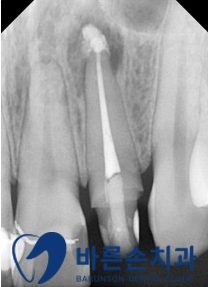

신경치료 완료 후의 치근단 사진입니다

여러번의 근관 소독 후

MTA 실러를 통하여 근관치료를 마무리 하였습니다

다행히 환자분의 통증도 없어지고, 고름주머니도 없어졌습니다.